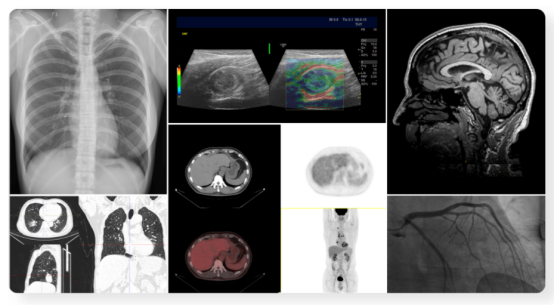

同时在影像阅片方面,该终端不仅可支持CT、MR、DX、XA、US、NM等多种传统影像类型,在提供丰富的图像浏览功能的基础上,还具备传统显示终端所不具备的核医学PET图像融合、MPR浏览、伪彩、ROI测量、HU值和SUV值测量等分子影像专用功能,系统可同时支持多终端的会诊模式,助力医院实现院内及上下级单位的影像学会诊,培训,高效解决患者病痛与医疗资源紧缺等问题。